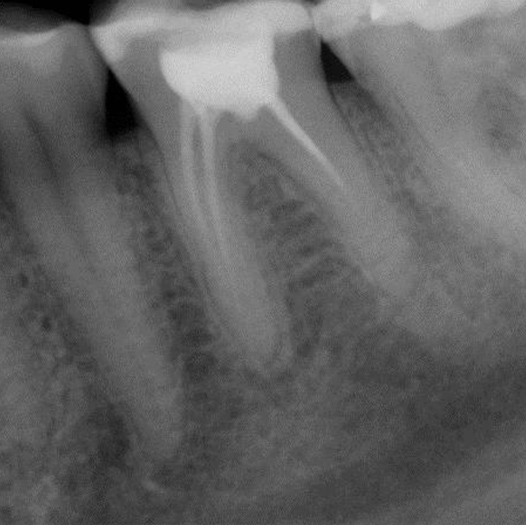

After

After Root Canal treatment